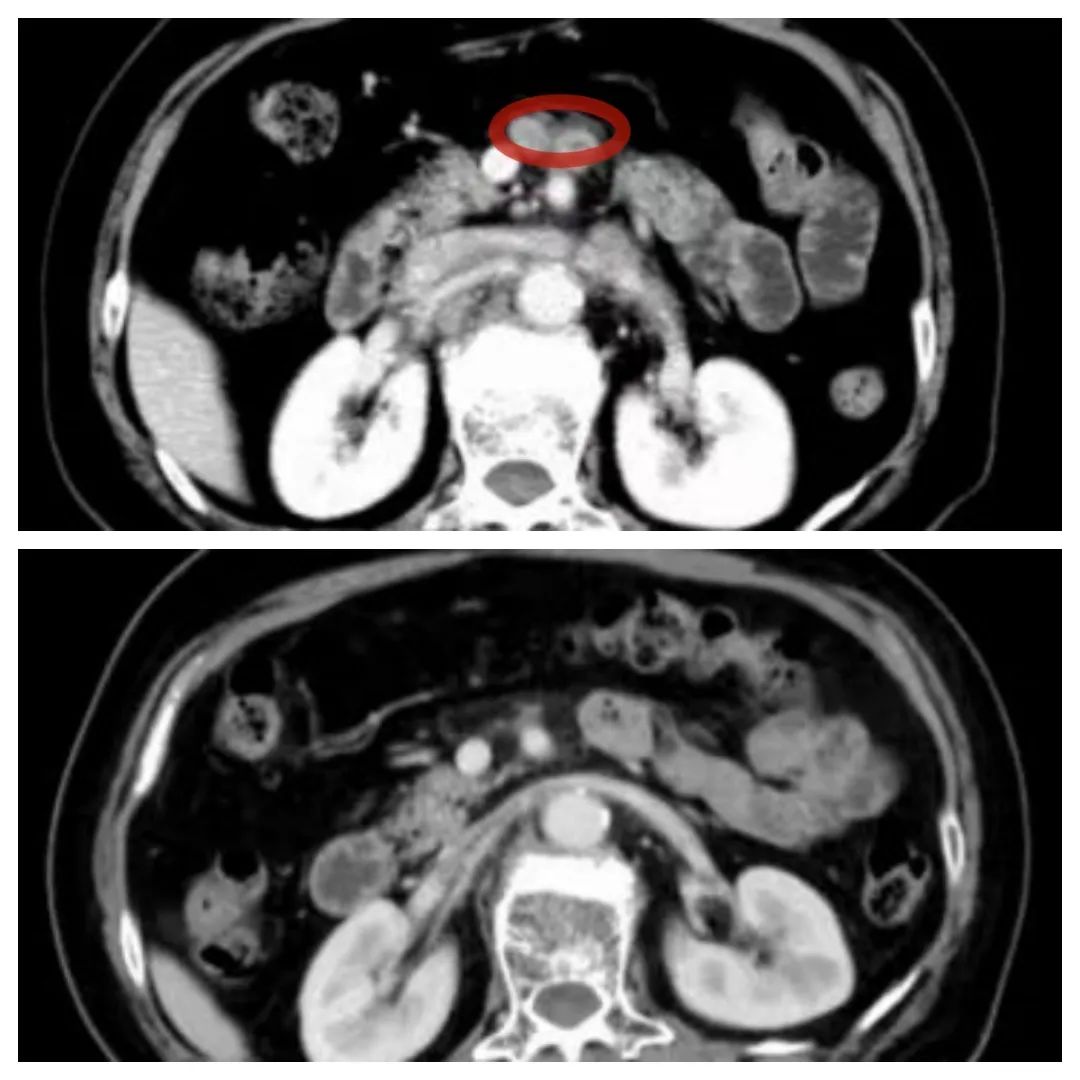

化疗前后对比(上图化疗前 下图化疗后)